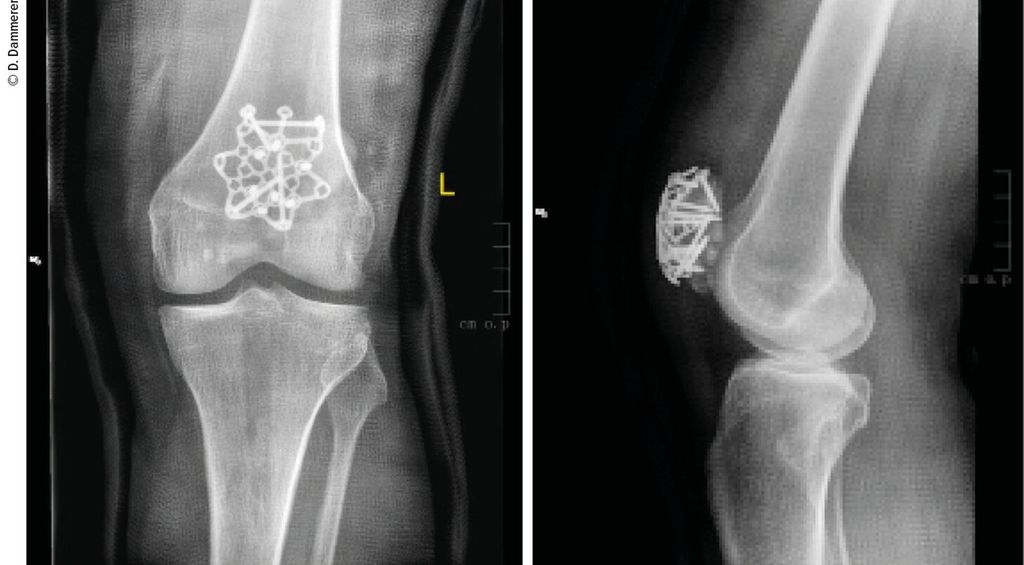

Abb. 1: Eine komplexe Mehrfragmentfraktur der Patella ergibt die Indikation zur operativen Versorgung

Abb. 2: Die operative Versorgung erfolgte mittels Sternplatte und zeigt ap und seitlich eine gute Reposition aller Frakturfragmente